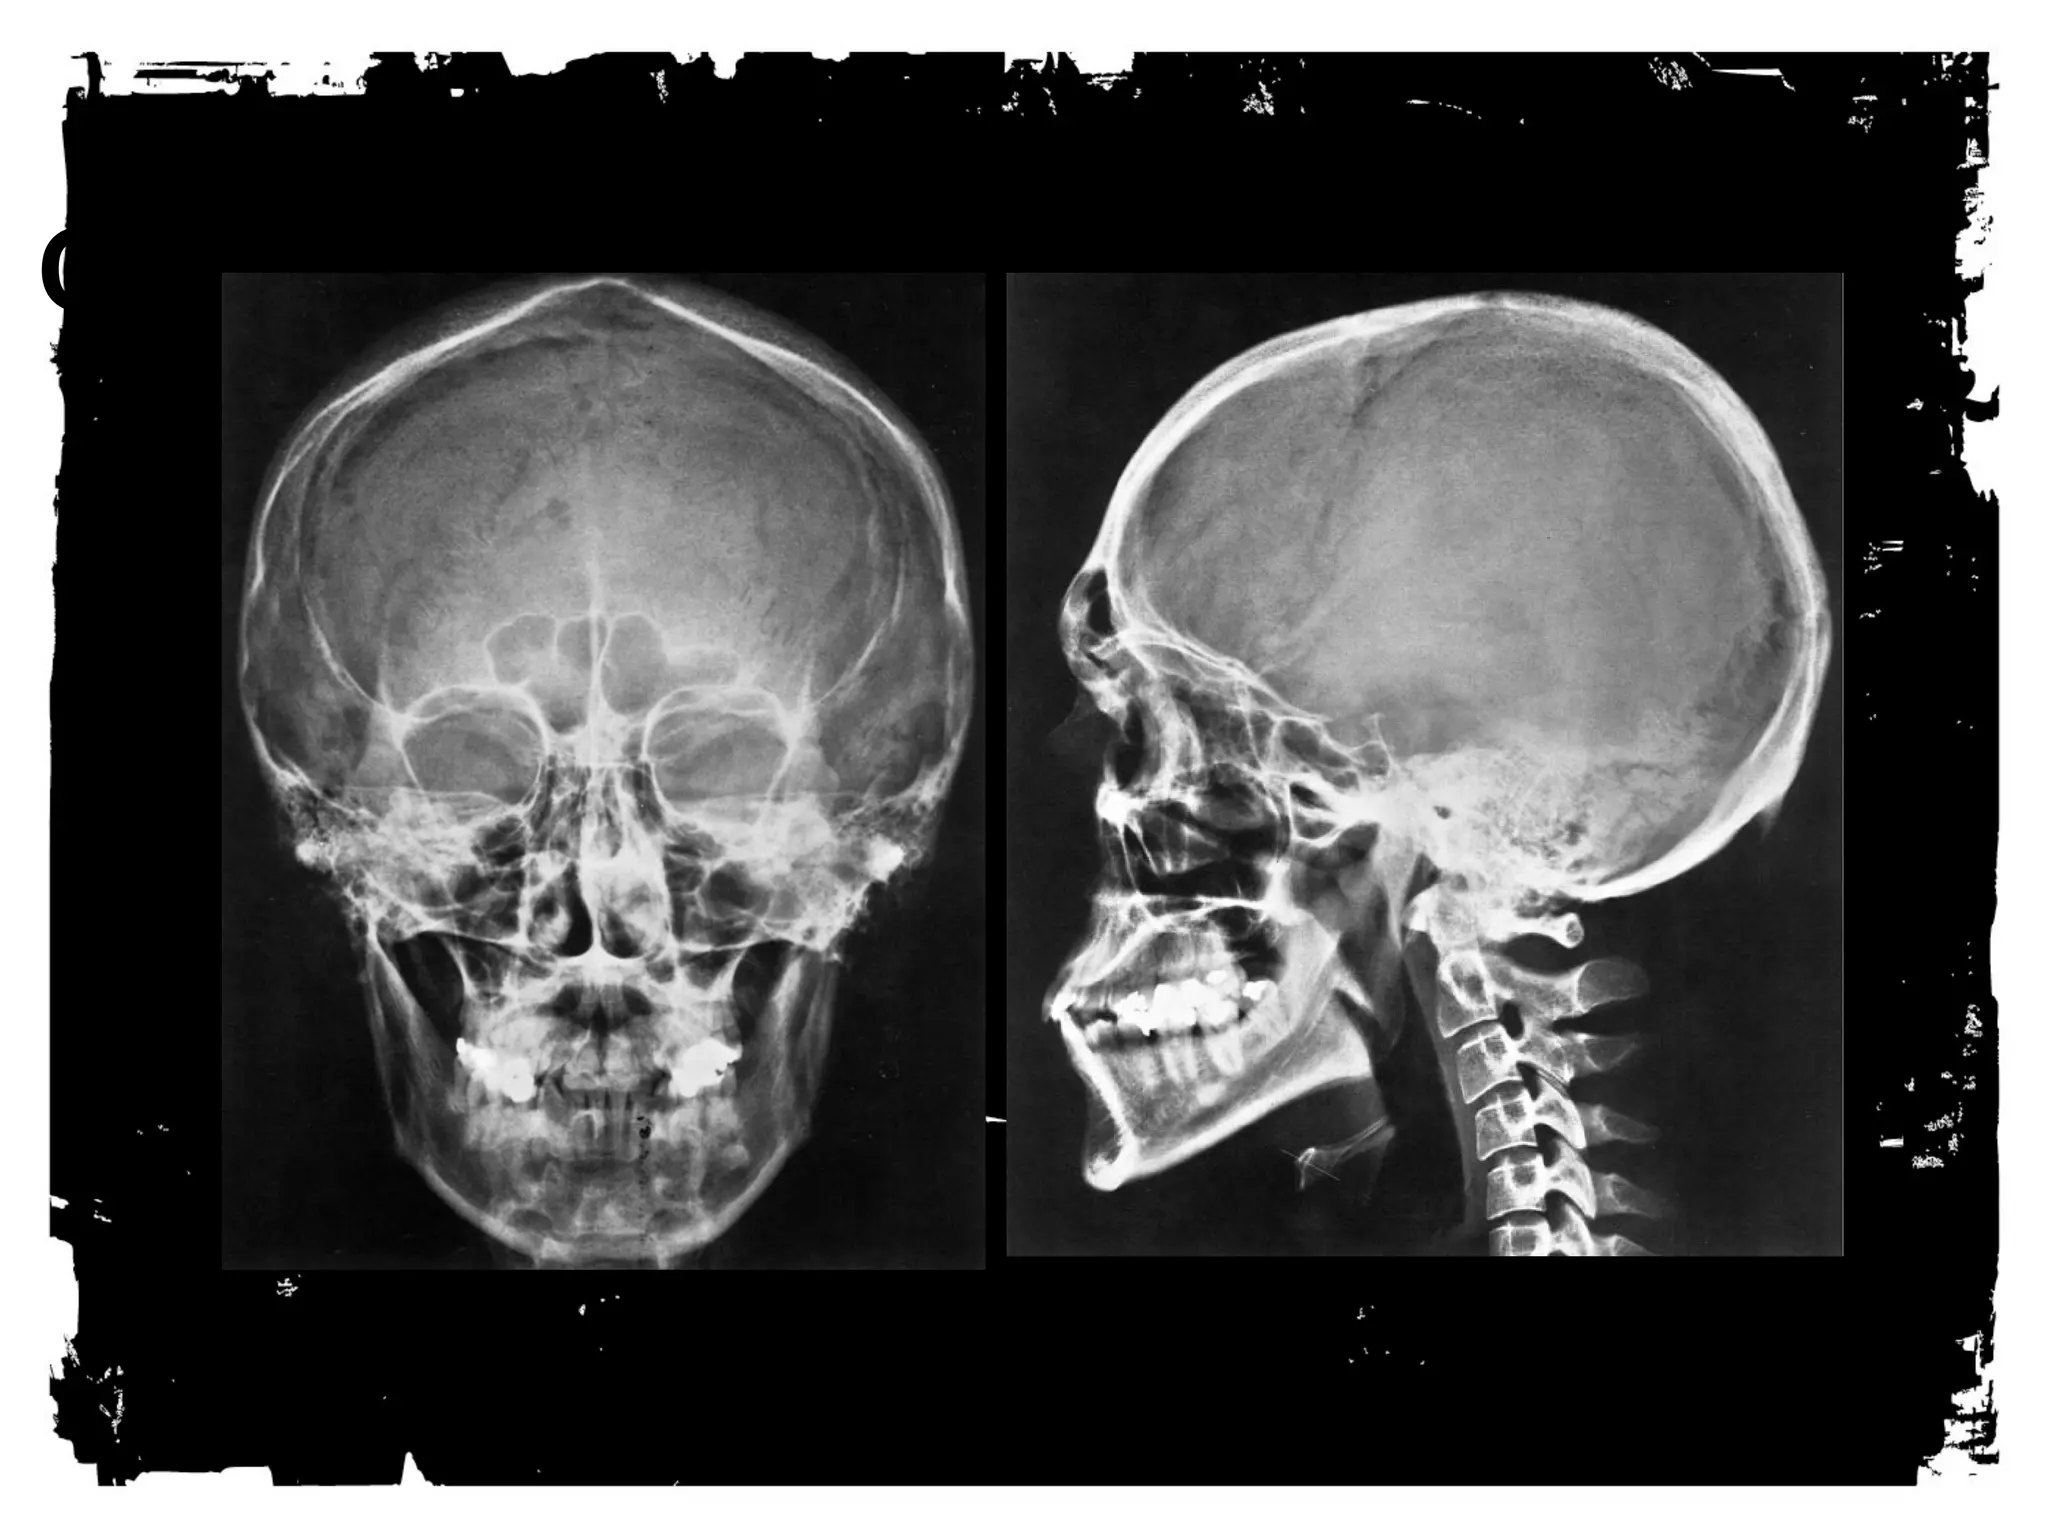

SYSTEMATIC INSPECTION

OF THE SXR

Step (1) : Scrutinize the site of the injury.

Step (2) : Look for:

Fissure fracture.

Depressed fracture.

Fluid level in the sphenoid sinus.

Step (3) : Look for less common finding (e.g.

pneumocephalus).

Fissure versus VM

Fissure black VM gray.

VM is branching.

VM has sclerotic edges.

Fissure versus suture

The fracture is more radiolucent

than the other sutures, has no

serration along its edges, and is

blind ending.

Depressed fractures are

often difficult to see. Look

for increased or double

density